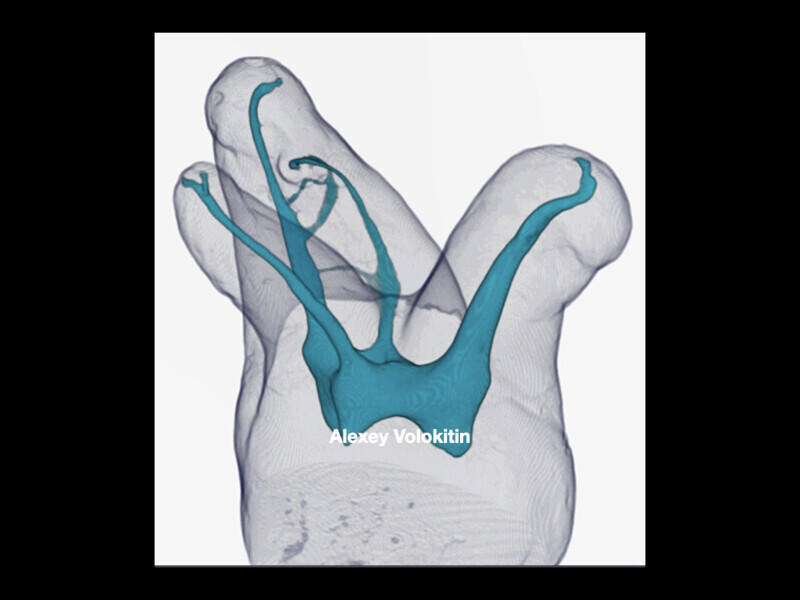

Clinical management of maxillary second molar root canal therapy in different anatomical situations